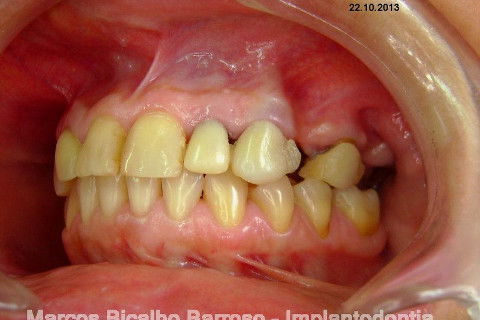

Paciente genêro feminino, 52 anos, procurou meus serviços para resolução de edentulismo parcial, insatisfação com ausência de dentes na região posterior esquerda da maxila, fratura de ponte fixa provisória...

Ao exame clínico já percebemos atrofia no rebordo, uma depressão na vestibular, indicação para enxerto ósseo e dente 27 com indicação para remoção. O plano de tratamento consistiu em levantamento de seio maxilar deste lado para possibilitar instalação de implante na região do 26 (não existe dente antagônico para oclusão com o 27), enxerto ósseo na vestibular do dente 24, aproveitamento do 22,23,25, em situação satisfatória, com indicação de confecção de novas coroas.

A minha intenção era levantamento de seio e enxerto na vestibular do 24 em única sessão, mas a pedido da paciente, resolveremos o caso por etapas, consideramos a prioridade da resolução desta região dos pré molares e fizemos esta cirurgia de hoje, usando osso autógeno coletado da região da tuberosidade e próximo do alvéolo do 27. Usamos também osso bovino liofilizado Bonefill (Bionnovation) granulação média, e tela de titânio Surgitime (Bionnovation). Não foi possível a instalação do implante em conjunto com o enxerto por considerarmos rebordo extremamente atrófico na espessura (menos de 2 mm na crista e menos de 3 mm até acima do terço médio).